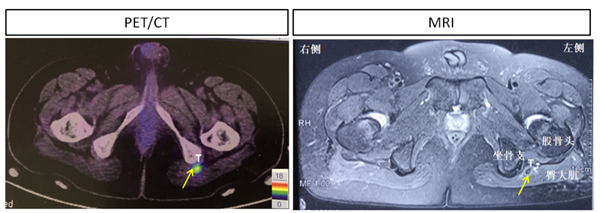

图2 利用68Ga-DOTA-NOC PET-CT显像定位诱导低磷性骨软化的软组织肿瘤

患者是一名30岁成年男性, 1年前无明显诱因双踝疼痛,行走时加重,渐发展至全身多处关节,双髋关节疼痛尤为剧烈,伴有肌肉无力,无法站立行走,夜间卧床翻身困难。曾辗转于省内多家知名三甲医院却无法确诊,进行常规对症处理,镇痛、消肿治疗,并无改善。困惑之中,患者慕名来我院就诊,内分泌科荆爱玉主任医师通过仔细问诊,体格检查,辅助实验室检查,考虑患者为“低磷性骨软化”,给予维生素D3及中性磷酸盐对症治疗,但2个月的疗程并未使患者骨痛、肌肉无力症状好转。通过进一步检查,发现患者左侧臀大肌近坐骨结节处有一个不到2公分的结节状软组织病变,且68Ga-DOTA-NOC摄取异常增高,提示为神经内分泌肿瘤(图2)。在众多的低磷性骨软化的原因中,肿瘤诱导因素非常罕见,唯一有效的治疗方法是手术切除。